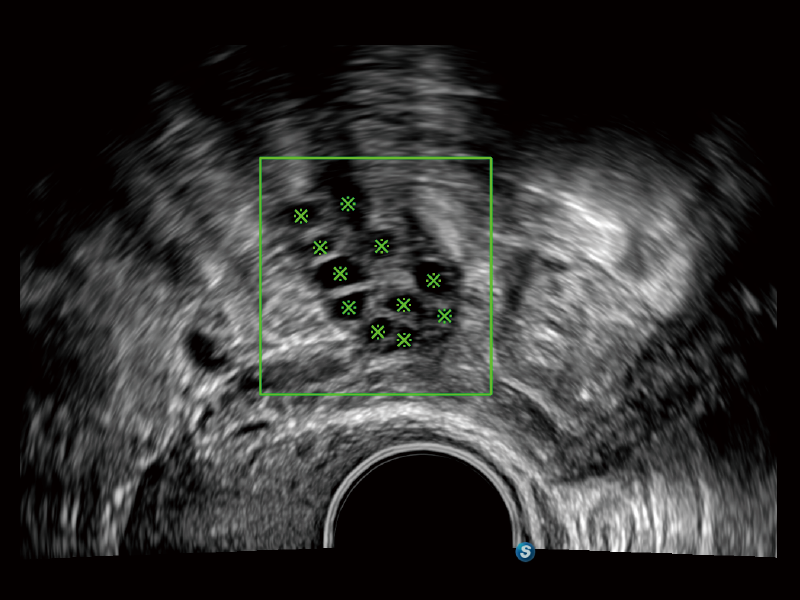

通过创新的Matrix E自适应滤波算法,能有效滤除软组织和噪声信号,最大限度保留超低速微细血流的信号;结合超长时间域算法,极大提升细微血流的敏感性和空间分辨率,更真实的反应组织、包块的血流灌注情况。